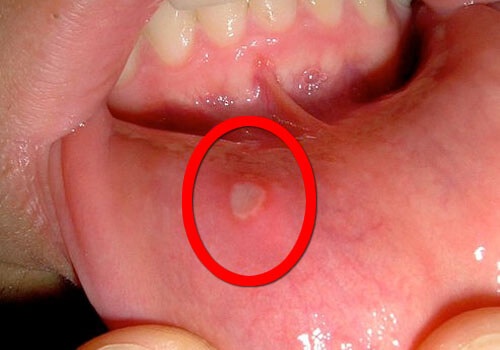

Когато говорим за този проблем, едно от най-важните неща, които трябва да знаем, е, че афтите са вид язва или отворена рана в устата. Афтите могат да бъдат бели или жълти и обикновено са обградени от ярко червена зона. Възможно е да се появят заради вирусни инфекции, но в някои случаи точната причина остава неизвестна.

- Червена, болезнена точка, която се превръща в язва;

- Язвата е жълтеникава на цвят;